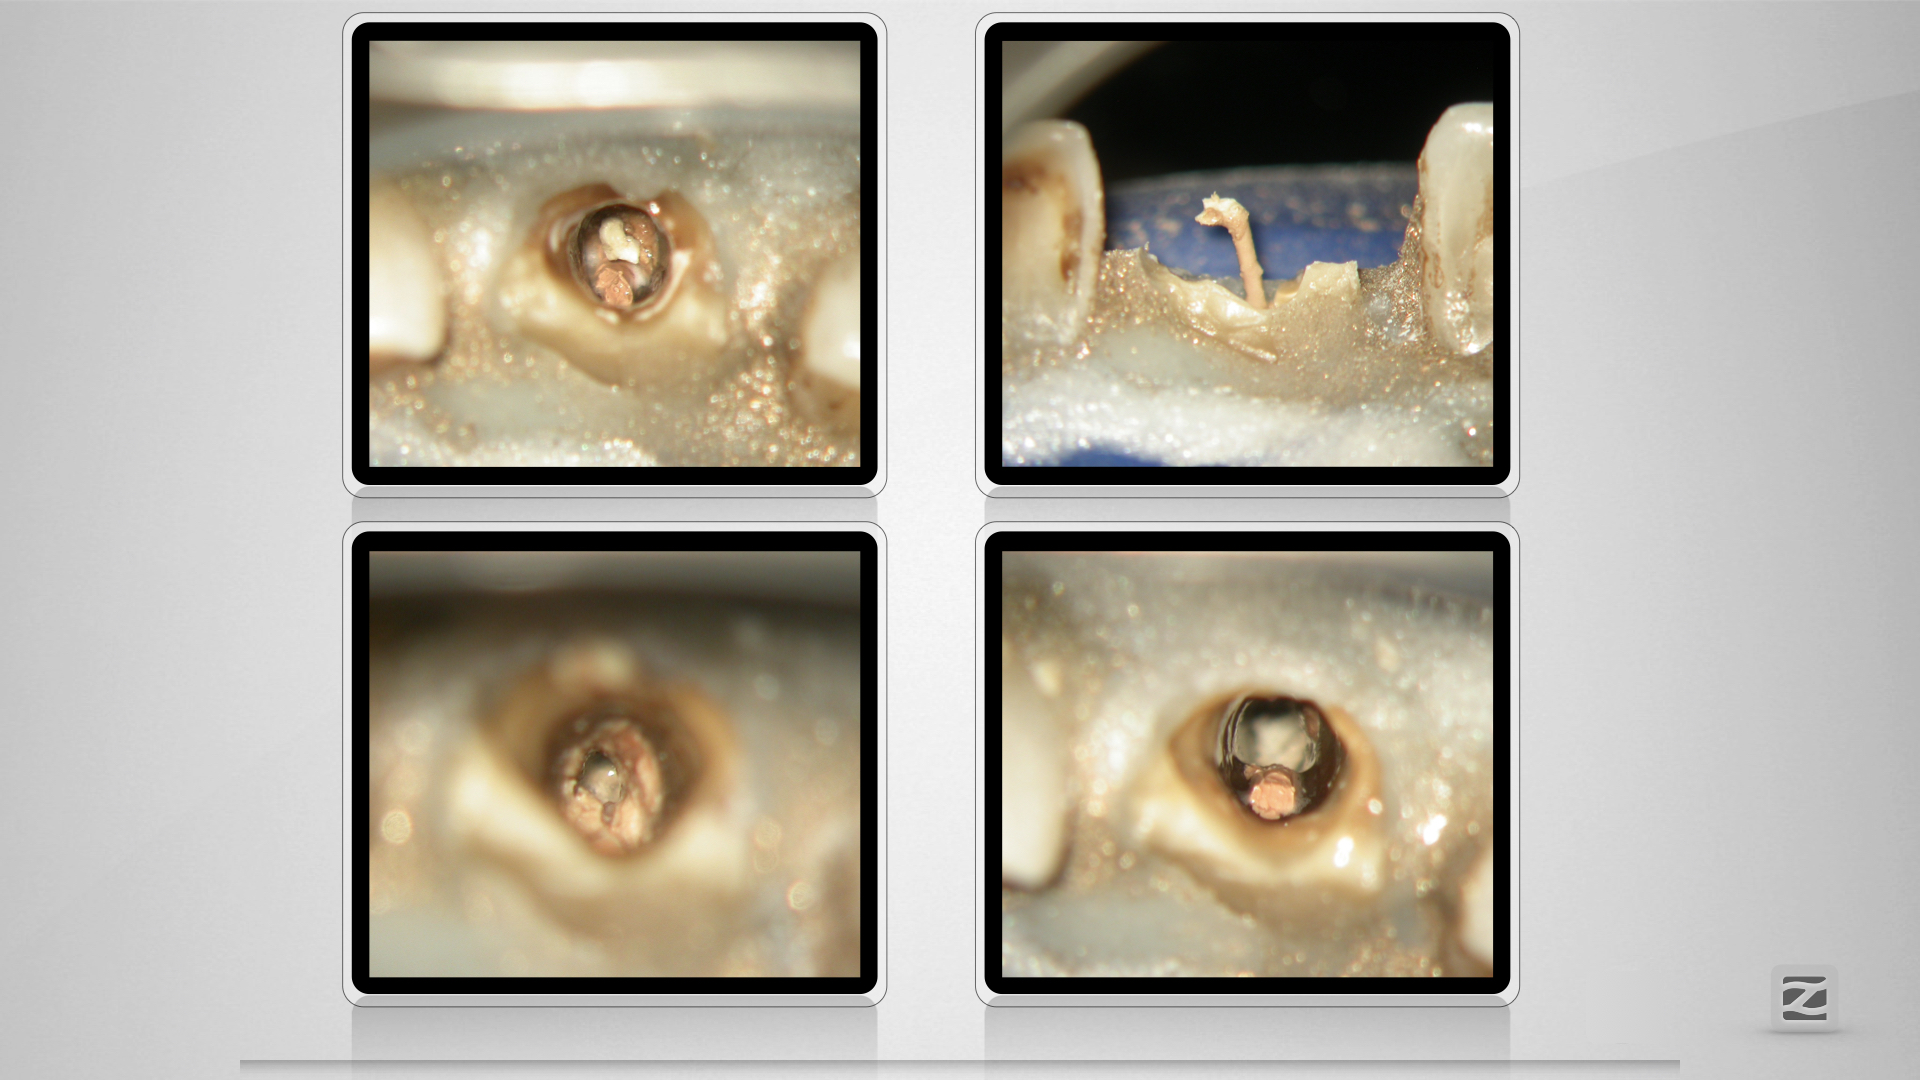

McFly! Jemand zuhause?